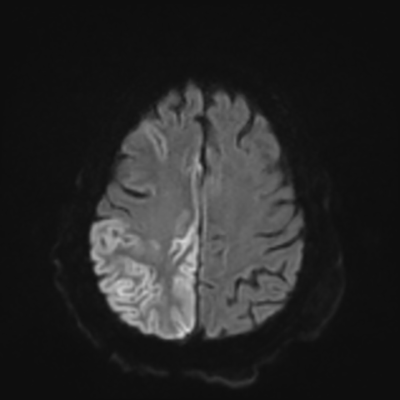

You come back the next day and see how things are going. The patient's electrographic record has shown a moderate encephalopathy (diffuse slowing, disorganization) with frequent right posterior quadrant delta slowing. Based on this result, and an adequately improved clinical examination, you give the okay to proceed with obtaining an MRI of his brain. This is shown below.

MRI brain (DWI)